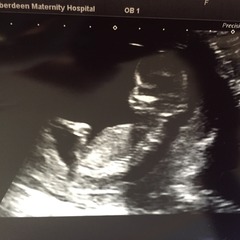

Jw35 · 25/01/2016 13:15

SmileSmileSmileSmileSmileSmileSmileSmileSmileSmileSmileSmile

Today is the best day of my life! New due date July 30th!! I'm 13+2! Woohoo! So happy! Baby wa wriggling about! Yay!

Brilliant pics Jw, we are due date buddies! I'm glad you had a good scan.

Congrats JW!! How very cute. Your DD looks so proud!

Sorry JW, must have missed the last page of posts. Great pics!! So happy for you Grin

jw what gorgeous pics of your perfect looking baby! love the one of your little girl too, so excited!

Jw hi baby! Great pics, your DD is super cute and looks like she's going to be a good big sis! So glad all went well.